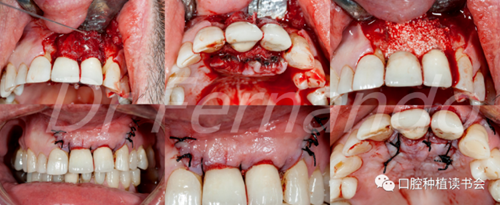

在治療種植體周圍炎方面,唯一有效的治療方法是進行外科手術(shù)(圖4 )。然而,手術(shù)治療只是部分有效;Leonhardt等人 描述在5年的時間里,超過一半的種植體周圍炎使用手術(shù)和抗菌治療是有效的。Heitz-Mayfield等 也證明,在短期(1年)內(nèi),用外科翻瓣加抗菌治療能夠有效地阻止90%的種植體周圍炎的發(fā)展;但在這些病例中,仍有50%的患者有探診出血。

圖4 前牙美學(xué)區(qū)種植體周圍炎采用手術(shù)&骨再生治療

盡管手術(shù)治療似乎能改善結(jié)果;但只有將手術(shù)治療和骨再生相結(jié)合才能獲得更高的成功率。Schwarz等人發(fā)現(xiàn)這種再生手術(shù)治療有2年以上的滿意效果,能使種植體周圍的骨吸收停止,探診出血率由80%降至34%(圖5 )。

圖5通過手術(shù)治療,種植體周圍獲得骨再生,術(shù)后2年效果穩(wěn)定(圖2、圖4相同病例)